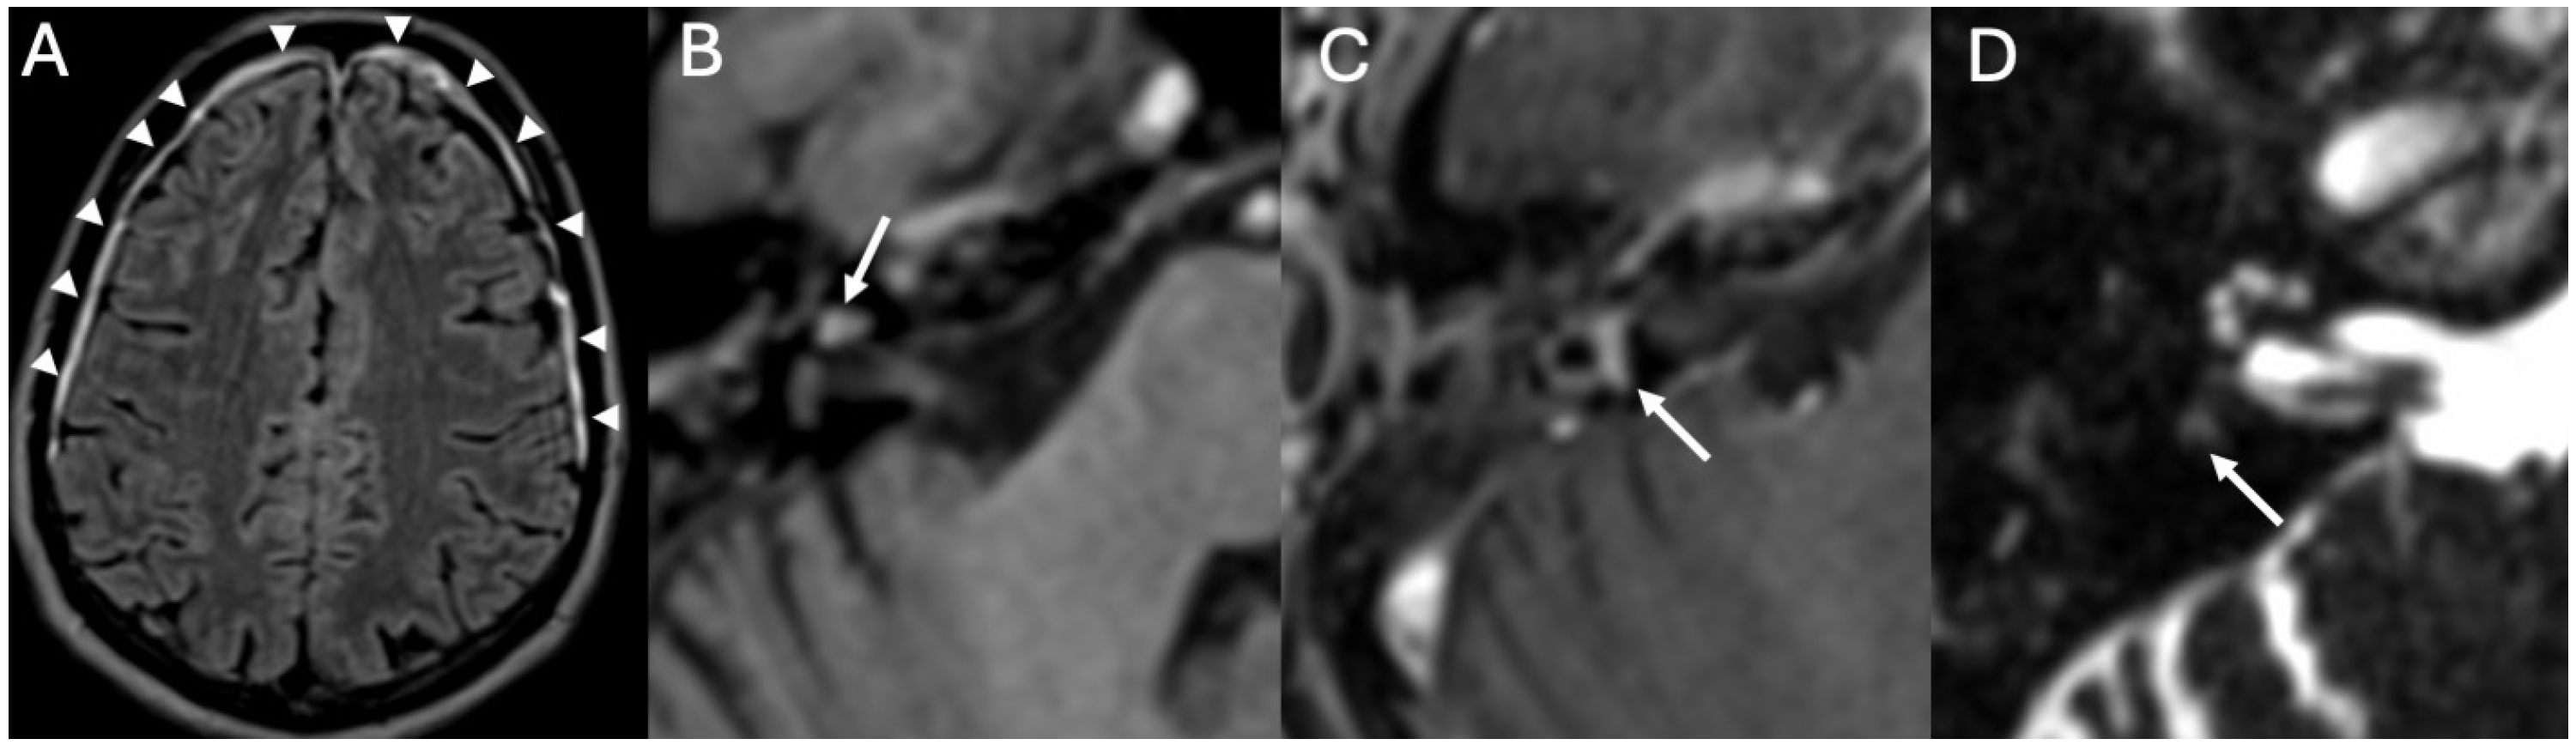

3.1. Otomastoiditis

3.1.1. Imaging